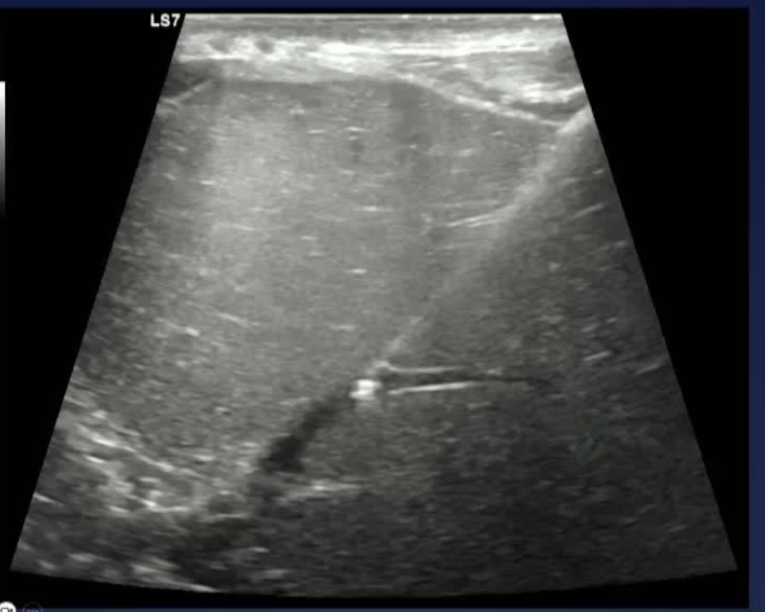

该程序包含以下步骤: 经脾脏入路:在超声引导下,刺穿脾静脉内的一个实质内分支。 在通过脾静脉造影确认了静脉通路后,导管和导丝被推进,以穿过脾静脉并抵达血栓化的门静脉。在门静脉/右门静脉分支处放置圈套器,为TIPS穿刺精准定位。TIPS穿刺圈套器,并穿过圈套器完成TIPS

步骤: 鉴于慢性血栓形成的复杂性: 一种经脾脏途径的门静脉再通术(PVR)。 随后是经颈静脉肝内门体分流术 。